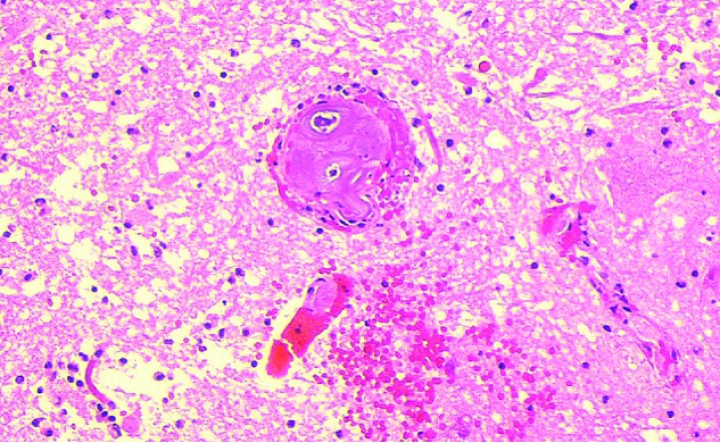

La mielopatía isquémica por embolismo fibrocartilaginoso ha sido descrita en medicina veterinaria de manera más frecuente en el perro, pero también en otras especies, así como en medicina humana.[ De Risio L. Platt SR. Fibrocartilaginous embolic myelopathy in small animals. Vet Clin North Am Small Anim Pract 2010;40:859-869. [PubMed] , Davidovic L, Illic N. Spinal cord ischemia after aortic surgery. J Cardiovascular Surg 2014;55:741-757. [PubMed] , Cuello JP , Ortega-Gutierrez S, Linares G et al. Acute cervical myelopathy due to presumed fibrocartilaginous embolism: a case report and systematic review of the literatura. J Spinal Disord Tech 2014; 27: E276-28. [PubMed] ] Se desconoce con exactitud la fisiopatología, pero en estudios histológicos e histoquímicos el material que se localiza en arteria(s) y/o vena(s) espinal(es) es idéntico al núcleo pulposo del disco intervertebral[ Cauzinille L. Fibrocartilaginous embolism in dogs. Vet Clin North Am Small Anim Pract 2000;30:155-167. [PubMed] ] (Fig. 2), por lo que se acepta que proviene de este, aunque se han descrito casos de embolismos por componentes del anillo fibroso.[ Neer TM. Fibrocartilaginous emboli. Vet Clin North Am Small Anim Pract. 1992 Jul;22(4):1017-26. [PubMed] ] Otras teorías indican que el material embolizado puede provenir de una degeneración metaplásica del endotelio vascular o de cartílago de crecimiento en animales jóvenes.[ De Risio L. Platt SR. Fibrocartilaginous embolic myelopathy in small animals. Vet Clin North Am Small Anim Pract 2010;40:859-869. [PubMed] ]

<p>Imagen de anatomía patológica de un émbolo fibrocartilaginoso en un vaso medular, correspondiente a otro caso. (Hematoxilina & Eosina, x20). Cortesía de M. Pumarola.</p>

Imagen de anatomía patológica de un émbolo fibrocartilaginoso en un vaso medular, correspondiente a otro caso. (Hematoxilina & Eosina, x20). Cortesía de M. Pumarola.